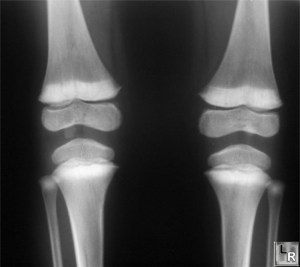

Regular measurement of blood lead in lead-exposed workers and the maintenance of blood lead levels below 1.9 umol/L (40 ug/dL) is advised.Lead-associated anemia is usually normocytic and normochromicand may be accompanied by basophilic stippling. Lead-induced peripheral demyelination is reflected by prolonged nerve conduction time and subsequent paralysis, usually of the extensor muscles of the hands and feet –wrist and foot drop. An increased density at the metaphyseal plate of growing long bones (“lead lines”) can develop in children and resemble those seen in rickets. Children with high-level lead exposure sometimes develop Fanconi’s syndrome, pyuria, and azotemia.Adults chronically exposed to lead can develop elevated serum creatinine levels, decreased creatinine clearance rates, and chronic changes and intranuclear inclusion bodies (detected at renal biopsy). ![]() |

1.9 umol/L (40 ug/dL) is advised.Lead-associated anemia is usually normocytic and normochromicand may be accompanied by basophilic stippling. Lead-induced peripheral demyelination is reflected by prolonged nerve conduction time and subsequent paralysis, usually of the extensor muscles of the hands and feet –wrist and foot drop. An increased density at the metaphyseal plate of growing long bones (“lead lines”) can develop in children and

resemble those seen in rickets. Children with high-level lead exposure sometimes develop Fanconi’s syndrome, pyuria, and azotemia.Adults chronically exposed to lead can develop elevated serum creatinine levels, decreased creatinine clearance rates, and chronic changes and intranuclear inclusion bodies (detected at renal biopsy).